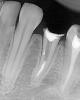

uzstom Опубликовано 15 августа, 2011 Поделиться Опубликовано 15 августа, 2011 Пацентка из России. Поставили анкер+композит. Сказали что нужно коронку поставить. Она к нам. Коффер несмог поставить , потому что культи не было (это оправдание). Знаю что можно и на такие зубы можно поставить, буду старатся. Что скажете на результат?111.bmp222.bmp Ссылка на комментарий

pawa Опубликовано 15 августа, 2011 Поделиться Опубликовано 15 августа, 2011 Ну, честно говоря, результат "после" не намного лучше, чем "до".+ угроза перфо.Не понятно, что Вы хотели продемонстрировать этим кл.случаем? Ссылка на комментарий

uzstom Опубликовано 15 августа, 2011 Автор Поделиться Опубликовано 15 августа, 2011 (изменено) угроза перфо это место от анкера что Вы хотели продемонстрировать этим кл.случаем?ни чего. Просто хочу узнать мнение форумчан, узнать свои ошибки и не делать их в дальнейщем. Изменено 15 августа, 2011 пользователем uzstom Ссылка на комментарий

Dzekhmd Опубликовано 16 августа, 2011 Поделиться Опубликовано 16 августа, 2011 ни чего. Просто хочу узнать мнение форумчан, узнать свои ошибки и не делать их в дальнейщем.Честно, я бы перепломбировала перед протезированием Почему не допломбировали до апекса, ведь файл до него дошел? Что апекс-локатор показывал на предпоследнем снимке? Ссылка на комментарий

uzstom Опубликовано 18 августа, 2011 Автор Поделиться Опубликовано 18 августа, 2011 Честно, я бы перепломбировала перед протезированием Почему не допломбировали до апекса, ведь файл до него дошел? Что апекс-локатор показывал на предпоследнем снимке? в снимке №2 с файлом АЛ показывал овер. 15 файл измерил - 13мм. Отступил на 1мм сделал упор до 35 размера. Ал показывал 2.3. Мастер гутта вошел на 12мм. Снимок в другой проекции. Ссылка на комментарий